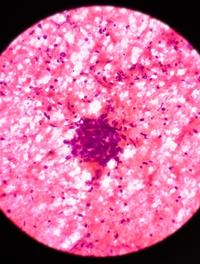

Les méningiomes sont les tumeurs primitives intracrâniennes les plus fréquentes chez l’adulte (40 % des cas). Ils se développent à partir de l’arachnoïde, un des feuillets des leptoméninges, situées à la face interne de la dure-mère. Le risque de développer un méningiome augmente avec l’âge et est deux fois plus élevé chez la femme que chez l’homme. Le traitement repose principalement sur l’exérèse chirurgicale.